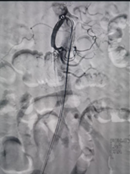

对此,普外科医师团队与多学科开展紧急会诊,并制定出最佳手术方案,决定为患者开展介入手术治疗致命肠系膜上动脉栓塞。在征求患者及家属同意后,普外科团队立即启动“绿色通道”,由副主任医师郭陵主刀,紧急为患者实施介入手术(肠系膜上动脉吸栓+肠系膜上动脉球囊扩张+肠系膜上动脉支架置入术),手术过程顺利。

术中取栓前后肠系膜上动脉造影对比

经过介入手术,患者堵塞的肠系膜上动脉即时完全开通,且患者腹部疼痛症状明显改善。